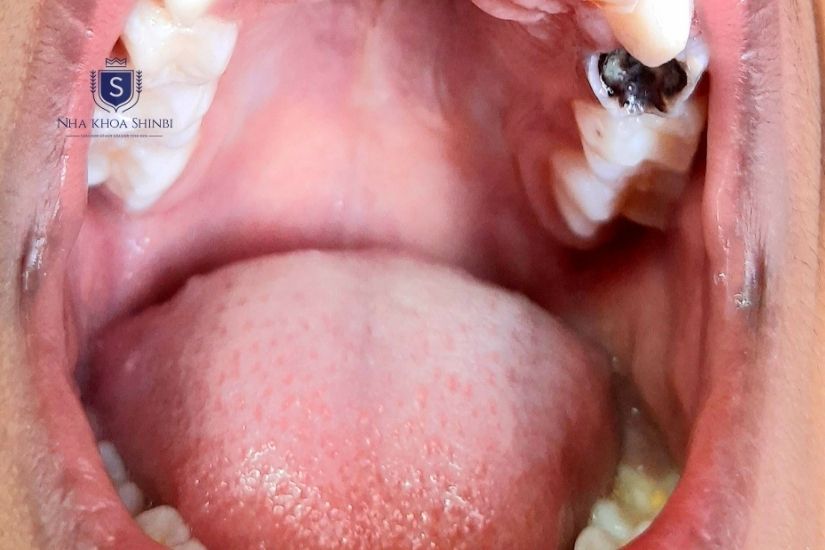

Răng số 6 hàm trên bị sâu nặng